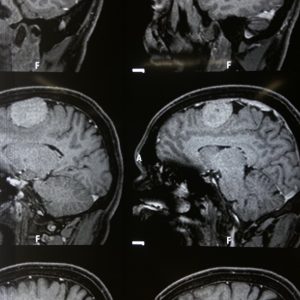

Photo Gallery